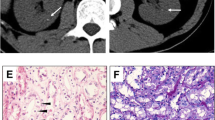

After admission, we monitored her blood pressure twice daily, which showed that the systolic blood pressure was within the range of 94–114 mmHg, whereas the diastolic blood pressure was within 55–70 mmHg. Electrocardiographic and echocardiographic evaluations were conducted for the patient. She also undertook an adrenal enhanced computed tomography (CT) scan.

Primary laboratory results of the proband are summarized in Table 1. Laboratory test showed severe hypokalemia, hypomagnesemia, hypocalciuria, and metabolic alkalosis, along with elevated renin activity. The electrocardiogram suggested sinus tachycardia (107 beats per minute), high voltage of the left ventricle, and ST-segment change of the anterolateral wall. An echocardiogram showed thickening of the left ventricular wall. The adrenal CT scan was unremarkable. The patient was diagnosed as GS based on her clinical phenotype. After the diagnosis, treatment with supplements of magnesium and potassium were introduced. She received 10% potassium chloride oral solution 20 ml taken orally twice daily, spironolactone 20 mg taken orally three times daily, and potassium magnesium aspartate 1 tablet taken orally three times daily. However, the electrolyte disturbances did not resolve completely, given the fact that treatment could only increase the level of potassium and magnesium up to the lower limit of the normal range. The patient had been followed up as outpatient at our endocrinology clinic for over two years since she was discharged. She denied any episode of tetany after accepting the treatment.